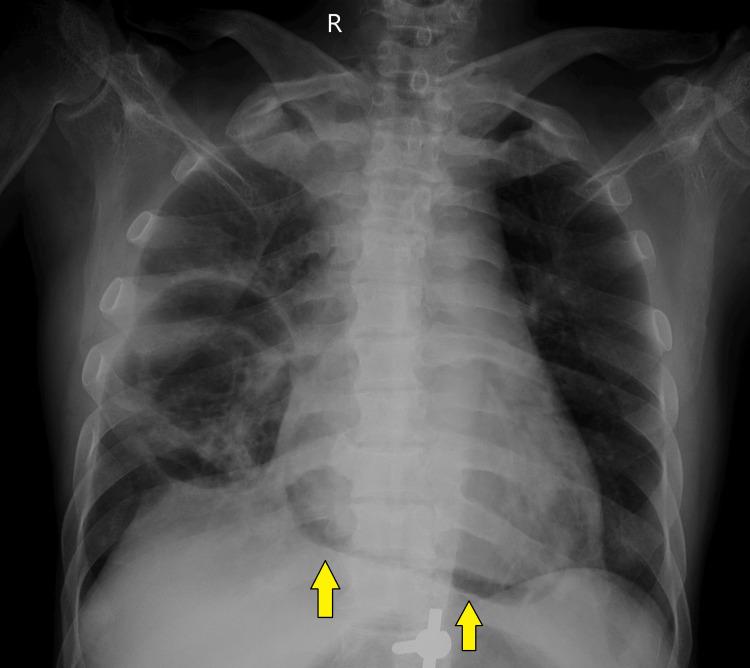

Pneumopericardium due to bronchopericardial fistula formation is a rare complication secondary to necrotizing pneumonia. Several such cases are reported due to different suppurative bacterial infections. Persistent fistulous communication has been reported to lead to tension pneumopericardium and hemodynamic instability, requiring urgent intervention such as pericardial drainage. A 41-year-old male patient, known to have chronic kidney disease and diabetes mellitus, presented with acute respiratory symptoms. Upon admission, the patient was febrile and required oxygen support via nasal prongs. A chest X-ray showed fibrocavitatory changes on the right side, with patchy air shadowing around the cardiac silhouette and a continuous diaphragm sign. A contrast-enhanced computed tomography (CECT) thorax revealed extensive areas of consolidation with necrotic areas within, forming a thin-walled cavity involving the right middle lobe. Also, suspicious communication of this cavity with the pericardial cavity along the right atrium was seen, with minimal pericardial collection and air foci within. The pleural fluid culture showed growth of . According to the antibiotic sensitivity report, the patient was started on IV meropenem and gentamicin for 21 days while monitoring kidney functions. The patient clinically improved on antibiotics, and follow-up radiological investigations showed resolution of pneumopericardium. In this patient, pneumopericardium was mild, and there was no evidence of tension pneumopericardium. Thus, conservative management with antibiotics was provided, with successful resolution. Unlike this case, if evidence of tension pneumopericardium had been present, emergency interventions for decompression would have been required, and these cases would have had a poor prognosis. This case demonstrates the importance of high suspicion and early diagnosis of pneumopericardium in patients with necrotizing pneumonia. Prompt treatment in these patients can prevent further life-threatening sequelae.

支气管心包瘘形成导致的气胸是坏死性肺炎继发的罕见并发症。已有数例因不同化脓性细菌感染导致的此类病例报道。据报道,持续性瘘管相通会导致张力性气胸和血流动力学不稳定,需要紧急干预,如心包引流。一名41岁男性患者,已知患有慢性肾病和糖尿病,出现急性呼吸道症状。入院时,患者发热,需要经鼻吸氧支持。胸部X线显示右侧有纤维空洞性改变,心脏轮廓周围有斑片状气影及连续膈征。胸部增强计算机断层扫描(CECT)显示广泛实变区域,内有坏死区域,形成一个累及右中叶的薄壁空洞。此外,可见该空洞沿右心房与心包腔可疑相通,心包内有少量积液和气灶。胸水培养显示……生长。根据抗生素敏感性报告,患者开始静脉输注美罗培南和庆大霉素21天,同时监测肾功能。患者使用抗生素后临床症状改善,后续影像学检查显示气胸已消退。在该患者中,气胸较轻,无张力性气胸证据。因此,给予抗生素保守治疗,获得成功治愈。与该病例不同的是,如果存在张力性气胸证据,则需要进行紧急减压干预,而这些病例预后较差。该病例证明了对坏死性肺炎患者高度怀疑和气胸早期诊断的重要性。对这些患者进行及时治疗可预防进一步危及生命的后遗症。